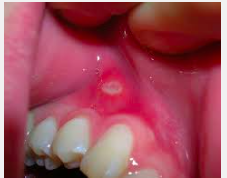

What are aphthous ulcers (canker sores)?

Superficial mucosal ulcerations more common in younger pts. that typically resolve within 7-10 days